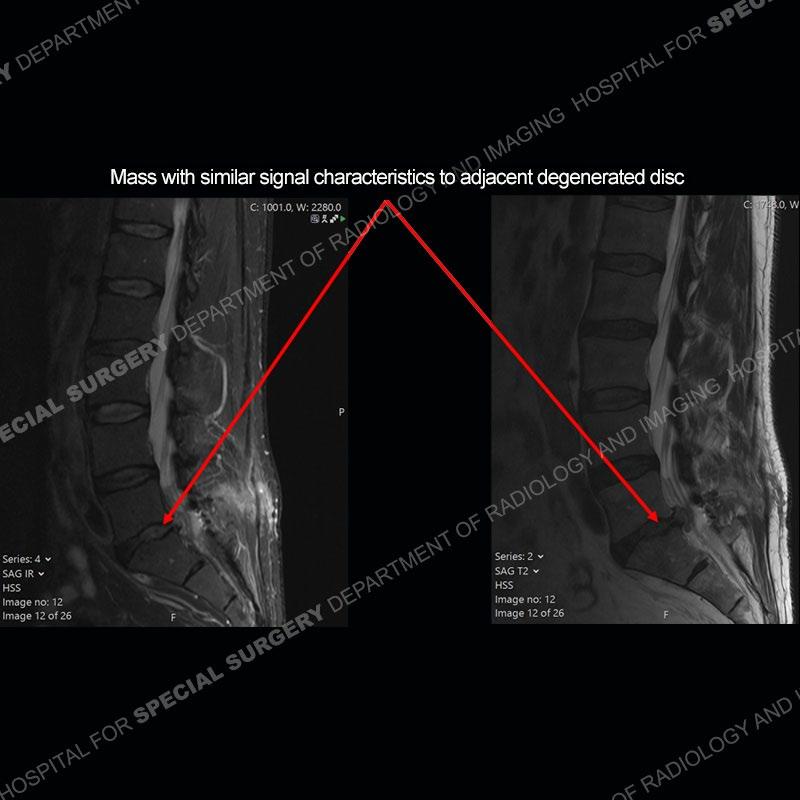

Post operative changes are seen on the left side at L5-S1 where there is near complete removal of the left sided L5 lamina, partial resection of the left L5-S1 facet joint, and resection of the left sided ligamentum flavum. In the anterolateral epidural space about the subarticular recess is a mass that demonstrates similar T1 and T2 signal characteristics to the adjacent degenerated disc. There is enhancement about the periphery of the mass, but the majority of this somewhat geographic or polyploid mass demonstrates no enhancement. The mass exerts prominent mass effect on the left S1 axillary sleeve/proximal nerve root. The left S1 nerve root shows enlargement and increased enhancement as compared to the contralateral right side.

Not as much of a diagnostic dilemma as some other cases but more so just a very nice example of what can be a difficult assessment at times. The evaluation of granulation tissue/scar/epidural fibrosis vs. disc herniation particularly in the earlier post operative period can be very difficult. Clues that can assist in identifying a disc herniation are a more geographic or polypoid nature to the mass, signal characteristics similar to the adjacent degenerated disc, mass effect upon the thecal sac/adjacent neural structures, and a typical enhancement pattern. As the disc material is avascular, as long as imaging is performed in a relatively rapid fashion after contrast administration (within 20-30 minutes), the granulation tissue around the disc will enhance but the disc material itself will not. If there is a marked delay between contrast administration and imaging, there may be diffusion of contrast into the disc making the assessment very difficult. The marked utility of contrast to help delineate disc vs. scar has led to our institution employing contrast fairly uniformly within the first two years following surgery.

The scar tissue in the setting of prior disc removal will be present in the anterior and anteriorlateral aspect of the epidural space. The signal characteristics can be somewhat variable from slightly more T2 hyperintense earlier on to T2 hypointense as the scar matures. However, the signal does not tend to follow the adjacent degenerated disc. The scar can produce mass effect, but it does not have to do so. In addition, at times the scar may be associated with a retraction of the adjacent thecal sac. Given the vascular nature of the scar there is typically somewhat avid, uniform enhancement which occurs fairly rapidly after contrast administration and begins to diminish within 20 minutes or so. Trying to discern the difference between scar and disc is of paramount importance given the rather poor outcomes associated with resection of scar as compared to disc material.